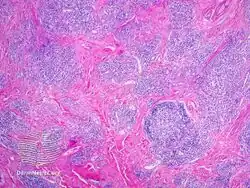

- IgG4-related skin disease pathology